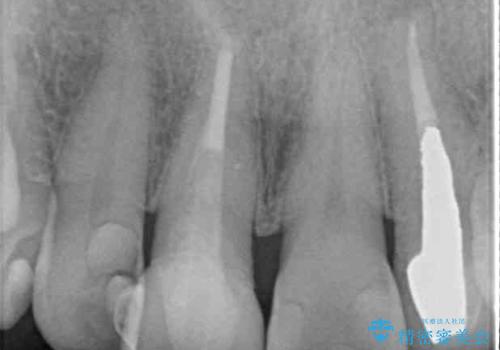

- 詰め物やクラウンで色合いが異なっている上顎前歯を気にして来院された患者様です。

長さや形を左右対称に整えたいとのことで、4歯をオールセラミッククラウンにて補綴治療を行うこととしました。